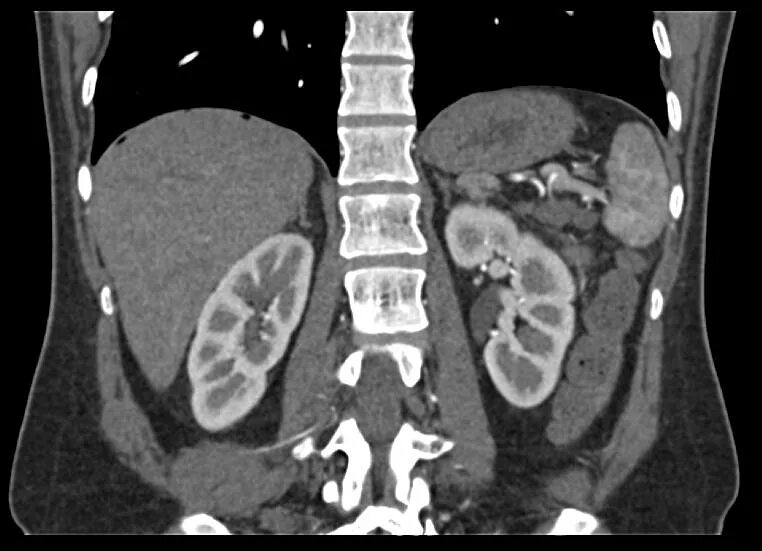

Мрт обп с контрастированием